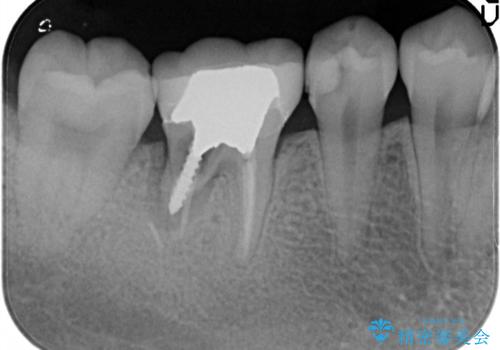

- 右下の奥歯の調子がよくないとのことで来院されました。

レントゲン・口腔内診査をお行い、保存が難しいことがわかりました。

抜歯後インプラントをする計画としました。

見た目では問題がなさそうでも、レントゲン撮影・診査を行うと状態が悪くなっていることがあります。